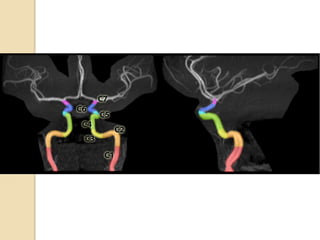

Arteries of the brain (lateral view) - MRA

1. Anterior cerebral artery

2. Anterior communicating artery

3. Basilar artery

4. branches (in insula) of middle cerebral artery

5. Cavernous portion of internal carotid artery

6. Cervical portion of internal carotid artery

7. Genu of middle cerebral artery

8. Intracranial (supraclinoid) internal carotid artery

9. Middle cerebral artery

10. Ophthalmic artery

11. Petrous portion of internal carotid artery

12. Posterior cerebral artery

13. Posterior cerebral artery in ambient cistern

14. posterior cerebral artery in interpeduncular

cistern

15. Posterior communicating artery

16. Posterior inf cerebellar artery.

17. Quadrigeminal portion of posterior cerebral

artery

18. Superior cerebellar artery

19. Vertebral artery